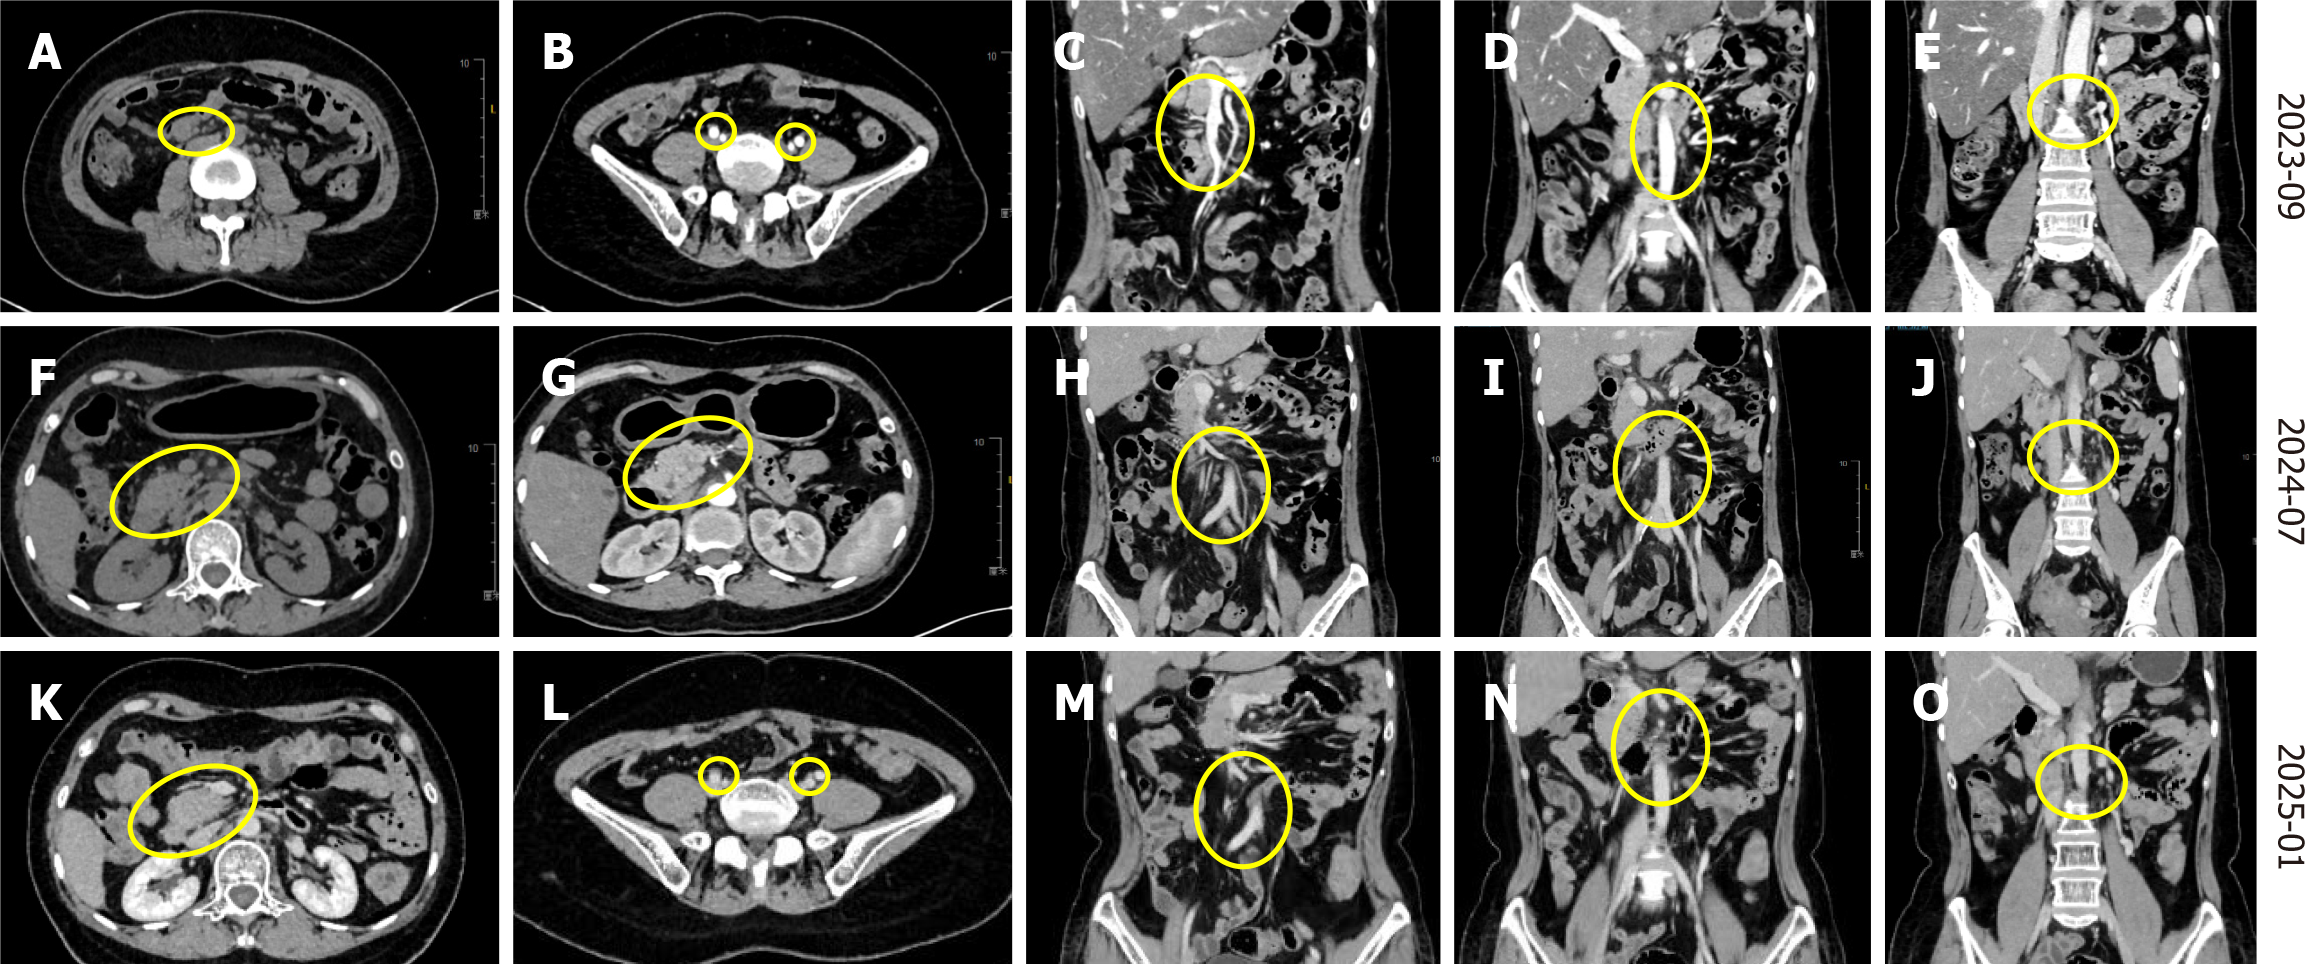

In August 2023, re-examination CT identified multiple enlarged lymph nodes in the abdominal cavity (Figure 2A-C). Subsequently, the pathological biopsy of the right abdominal mass was performed and immunohistochemical examina

In August 2023, re-examination positron emission tomography (PET)-CT showed multiple enlarged lymph nodes in the abdominal cavity, which were considered manifestations of DLBCL based on immunological results as determined by a multidisciplinary team. According to the basic treatment principles of multiple primary tumors of the Chinese Society of Clinical Oncology Guidelines in 2024[4] and the National Comprehensive Cancer Network Clinical Guidelines in 2024[5], the patient was put on the standard first-line treatment Rituximab, cyclophospha-mide, hydroxydaunorubicin, Oncovin (vincristine) and prednisolone (R-CHOP) regimen chemotherapy, consisting of rituximab 600 mg/day 1, cyclo

From September to December 2023, the second to sixth cycles of R-CHOP chemotherapy were administered as follows: Rituximab 600 mg/day 1, cyclophosphamide 1000 mg/day 1, pirarubicin 70 mg/day 1, vincristine 2 mg/day 1, and prednisone 100 mg/day 1-5. After the second cycle of R-CHOP chemotherapy, CT revealed a significant reduction of the lymph nodes in the abdominal aorta, bilateral iliac vessels and abdominal compared to earlier tests. The therapeutic effect of the drugs was evaluated as the partial response (PR). However, the complete response (CR) was achieved on the sixth cycle of chemotherapy. In January 2024, the treatment was changed to rituximab 500 mg/day 0, etoposide 0.15 g/day 1-3, ifosfamide 8 g/day 2, carboplatin 0.5 g/day 2. These drugs achieved significant bone marrow suppression. In February 2024, the chemotherapy dosage was adjusted to rituximab 600 mg/day 0, etoposide 0.15 g/day 1-2, 0.1 g/day 3, ifosfa

From April to June 2024, the patient underwent four cycles of chemotherapy comprising 600 mg zuberitamab and gemox regimen (gemcitabine 1.7 g/day 1, oxaliplatin 170 mg/day 1 q2w). After the last chemotherapy cycle, the patient developed grade III bone marrow suppression. In July, a follow-up CT showed a marked reduction in the abdominal tumor and the therapeutic effect evaluation was PR. The patient was administered with a fifth round of chemotherapy including 600 mg of zuberitamab and gemox regimen (gemcitabine 1.0 g/day, oxaliplatin 150 mg/day 1 q2w) and lenali

Following the diagnosis of DLBCL in August 2023, which was treated with the R-CHOP regimen chemotherapy, a follow-up abdominal CT after the second cycle of chemotherapy confirmed that the lymph nodes in the abdominal aorta, bilateral iliac vessels and abdominal were significantly resolved compared to earlier tests, and the therapeutic effect was evaluated as PR (Figure 3A-E). Notably, the therapeutic effect was only evaluated as CR at the sixth cycle of chemothe